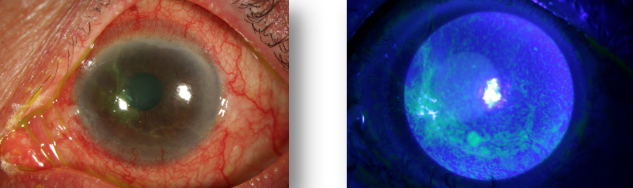

6. Corneal epithelial lesions can also be secondary to systemic immune system diseases. Autoimmune diseases such as Sjogren's syndrome and secondary Sjogren's syndrome caused by rheumatoid arthritis are easy to cause long-term immune inflammation on the ocular surface, leading to corneal epithelial erosion.

Figure 7. A 52 year old female patient has red eyes, sand sensitivity and photophobia for more than 3 years, and has a history of rheumatoid arthritis for 10 years; Schirmer test of both eyes: 0mm/5min, tear film rupture time of both eyes: 1s. It is corneal epithelial injury caused by autoimmune diseases.